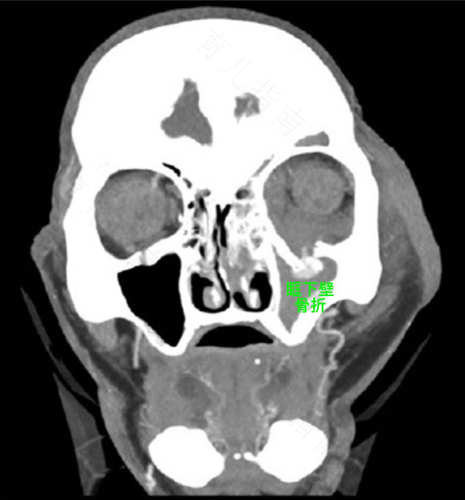

1、眶骨折如果引起孩子眼睛不对称大,可能是骨折有移位情况,需要手术治疗。先去医院拍X光片检查确定骨折程度。不要过度活动,不要揉眼或挤压患处,如果X光片检查移位严重,最好尽早手术治疗。

2、眼眶骨折后,如果骨折处出现畸形,或者出现游离性骨折,一般是需要治疗的。现在需要明确骨折的具体情况,如果是上述情况,导致两个眼睛大小不同,一般需要固定。

2、般来说这种眼眶的骨折往往就是出现那种骨折线,而并没有出现那种错位,是不需要进行处理的,并且一般的市级医院也处理不了。